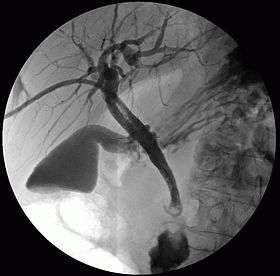

Cholangiography

Cholangiography is the imaging of the bile duct (also known as the biliary tree) by x-rays. There are at least two kinds of cholangiography:

- percutaneous transhepatic cholangiography (PTC): Examination of liver and bile ducts by x-rays. This is accomplished by the insertion of a thin needle into the liver carrying a contrast medium to help to see blockage in liver and bile ducts.

In both cases fluorescent fluids are used to create contrasts that make the diagnosis possible. Cholangiography has largely replaced the previously used method of intravenous cholangiography (IVC).